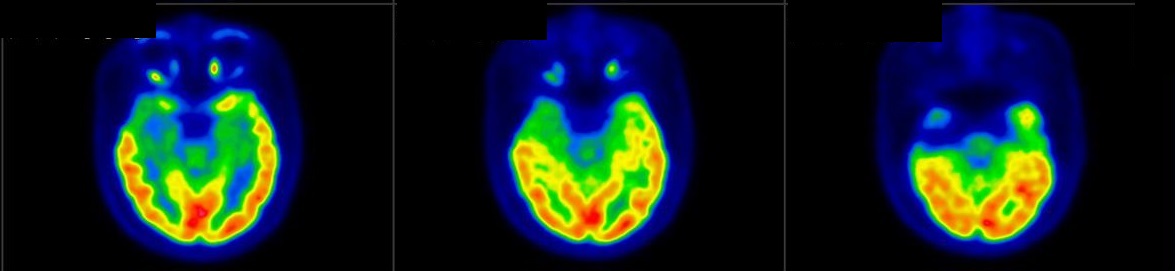

脑神经科

![]() [C-11] PIB |

![]() [C-11] Raclopride |

![]() [F-18] DOPA |

脑神经疾病